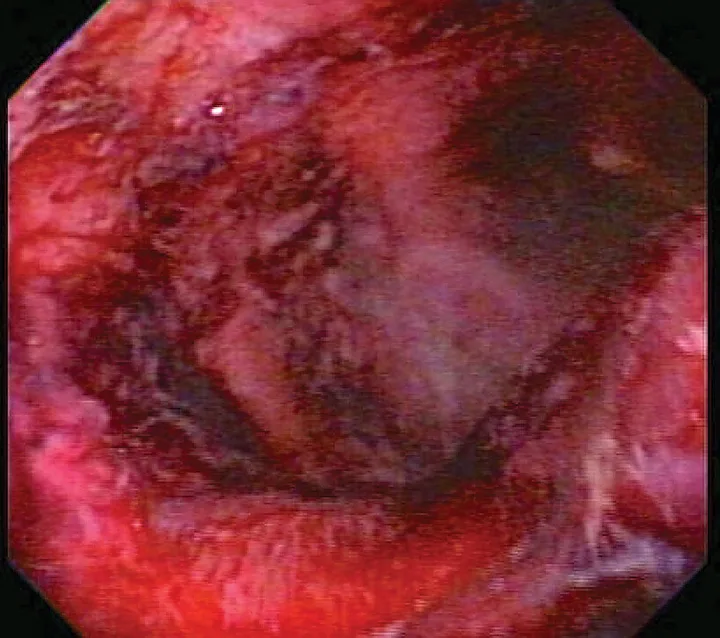

Butorphanol (for sedation) and furosemide (a potent loop diuretic) are common initial treatment choices for patients presented with acute congestive heart failure. Both injectable medications can be given intravenously or intramuscularly, but they cannot be combined. Furosemide is a mildly alkaline, buffered product and should not be mixed with solutions that have a pH less than 5.5; the pH of butorphanol varies between manufacturers but may be between 3.0 and 5.5.8,12,13 When these drugs are allowed to interact through combination in a syringe or an IV line, a cloudy precipitate may form (Figure 1, above). This precipitate can damage tissue or occlude a vessel—particularly in the cerebral and pulmonary vasculature, which can be life-threatening—and one or both drugs may be ineffective. To prevent this interaction, drug compatibility should always be determined prior to combination (in a syringe) or coadministration of drugs in any fluid lines; in addition, the fluid line should be thoroughly flushed with a compatible solution between administration of each drug.

Critically ill patients are susceptible to GI ulceration (Figure 2) because of many factors, including primary or secondary GI disease, surgery, hypoperfusion, and mechanical ventilation. These patients also often require corticosteroids or NSAIDs because of inflammation, pain, and adrenal or immune-mediated disease. Ulceration can result in GI dysfunction, hemorrhage, and/or perforation.

FIGURE 2

Endoscopic image of duodenal ulcers in a critically ill patient